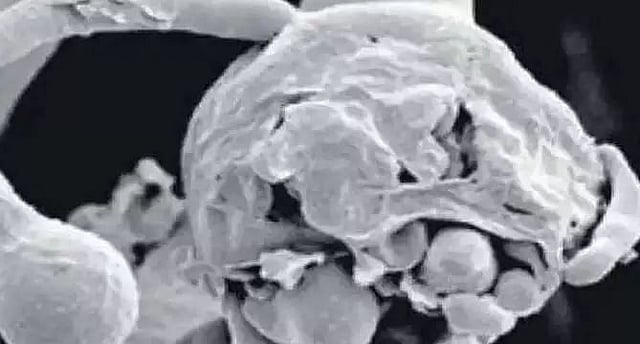

Alarming White Fungus Infection: As India grapples with alarmingly rising cases of the Black Fungus (Mucormycosis disease) after battling severe oxygen shortage amidst the second wave of the pandemic, the heath fraternity is now concerned with White Fungus which is being reported among Covid-recovered patients who are on long-term steroid use and suffer from severe uncontrolled diabetes, among other conditions.

White Fungus has generally been seen in immuno-compromised people like those on chemotherapy or undergoing bone marrow transplant.

"White Fungus usually referred as to infection from Candidiasis. It is usually seen as an opportunistic infection among immune compromised host such as patients with HIV, on anti-cancer therapy, on long-term steroid use or severe uncontrolled diabetes," said Harshal R. Salve, Associate Professor at the Centre for Community Medicine, AIIMS, New Delhi.

The White Fungus is a condition that may affect not just Covid patients, but any patient with a significant impairment of immunity.